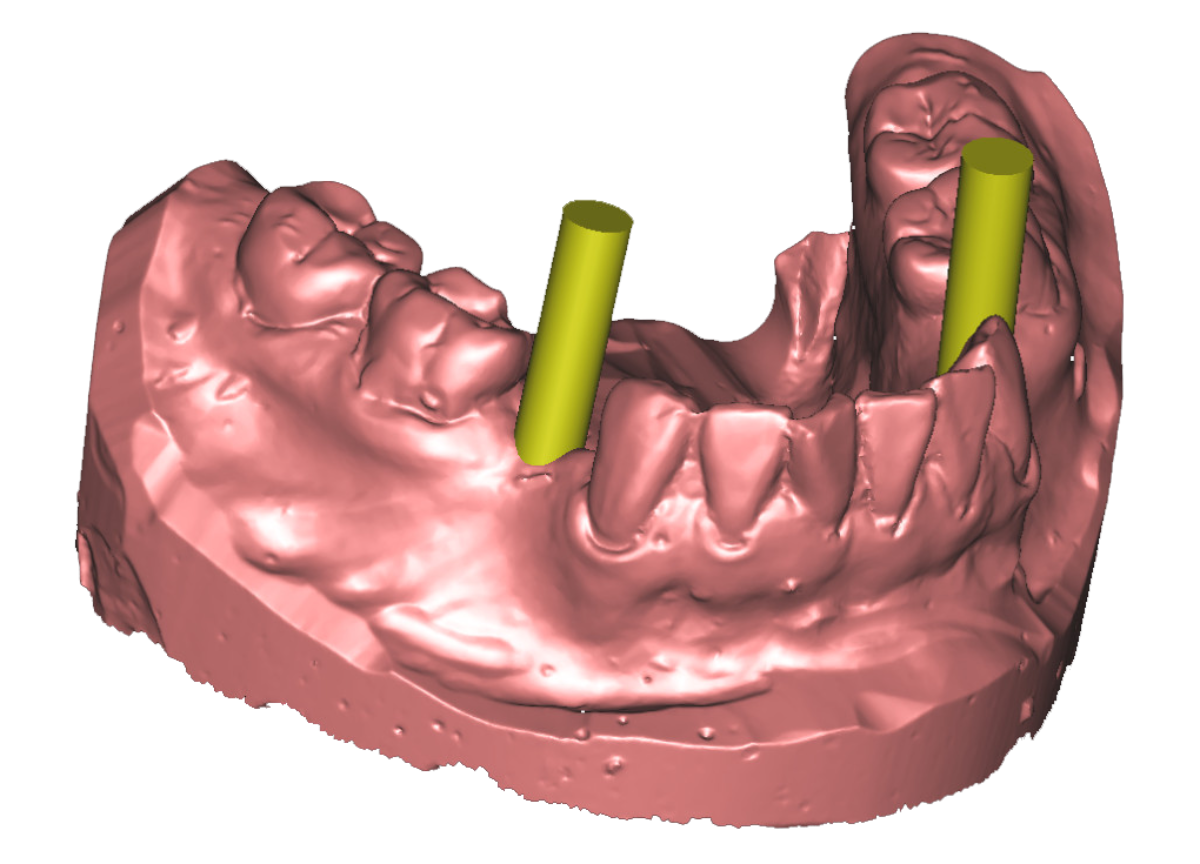

An Hand von vorliegenden dreidimensionalen Befunddaten ( 3D- Röntgenbild -DVT/ digitalisiertes Kiefermodell) wird vor dem eigentlichen Eingriff am Computer mit einer speziellen Software eine virtuelle Implantation durchgeführt ( Simulation der geplanten Operation) und auf Basis der ermittelten Daten eine Bohrschablone für das Setzen der späteren Implanate in Auftrag gegeben. Vorteile des Verfahrens sind : klinische Umsetzung und Reproduzierbarkeit der gewünschten Implantatpositionen Ermittlung des eventuell erforderlichen Bedarfs an knochenaufbauenden (augmentativen) Maßnahmen maximale Schonung benachbarter anatomischer Strukturen vor unbeabsichtigter Verletzung (Nachbarzähne, im Operationsgebiet verlaufende Nerven, Kieferhöhle etc.) Umsetzung der in der virtuellen Planung in funktioneller und ästhetischer Sicht als optimal ermittelten Implantatposition ; die individuelle intraoperative Korrekturmöglichkeit bleibt jeder- zeit gegeben Verkürzung des operativen Eingriffs durch die präoperative Operationsplanung

umfangreiche virtuelle Operationsplanung 3-D Implantatplanung Operationsschablone - angefertigt  nach virtueller Implantation umfangreiche virtuelle Operationsplanung umfangreiche virtuelle Operationsplanung

Virtuelle Implantation (Operationsplanung) am Computer